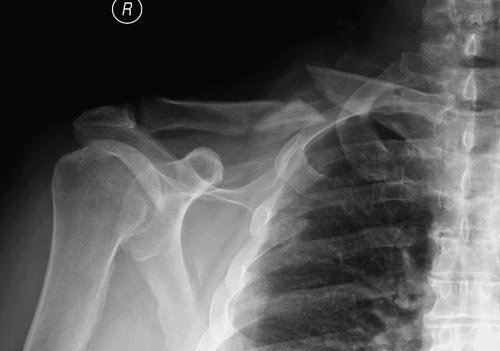

Болезненные ложные суставы надо оперировать, и здесь представлен случай

свежего болезненного ложного сустава, оперированного через 4 месяца.

Освобожден средний фрагмент и боковая компрессия лагированием, фиксация

пластиной..